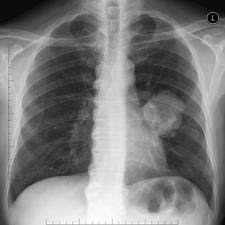

- Ho kéo dài là triệu chứng sớm của ung thư phế quản